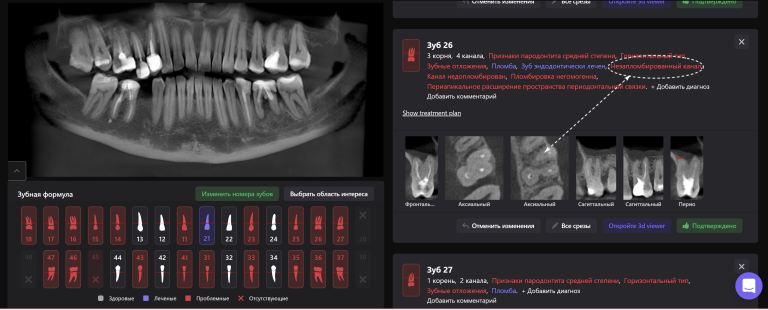

Для принятия клинического решения врач проанализировал данные осмотра и рентгенологического отчета Diagnocat. В отчете содержится оценка ранее проведенного лечения и данные о наличие признаков периапикальных изменений

Обратите внимание на высокий процент вероятности, который предлагает Diagnocat. Принято решение о сохранении зубов и проведении повторного эндодонтического лечения

«Эндодонтический отчет» Diagnocat помогает зафиксировать изначальный объем периапикального очага и изучить анатомию и морфологию корневых каналов до начала лечения